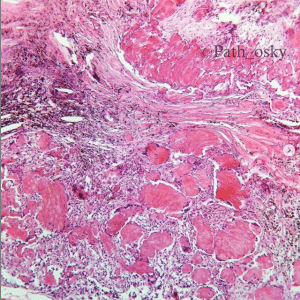

Anatomía Patológica

- Neuropatología

- Hematopatología

- Citopatología

- Asociación entre pronóstico y presencia de receptores PD-L1 en pacientes con tumores del sistema nervioso central.